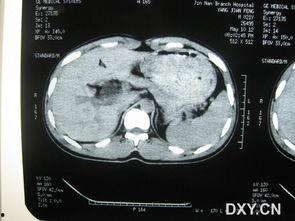

2. 影像学检查:比如CT、MRI等,可以更清晰地看到囊肿的位置和大小。